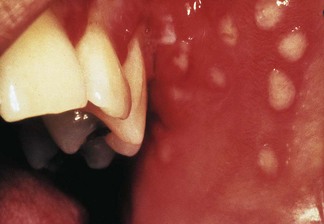

The nomenclature of herpesviruses is contentious; there is thus a historical or a traditional (trivial) nomenclature and an official name for each virus (Table 4.3). The herpesviruses that commonly infect humans can be distinguished by their antigenic and genomic profiles, although they cannot be differentiated by electron microscopy owing to identical capsid morphology. They also have a universal ability to establish latent infection in the host in which they reside, and manifest a number of common epidemiological features. Herpes simplex virus, herpes zoster virus, Epstein–Barr virus, human cytomegalovirus and herpesviruses 6 and 8 can all cause infections in oral and perioral tissues (Fig. 4.4); see Chapter 35 for details.

Fig. 4.4 Primary herpes simplex infection of the oral mucosa.